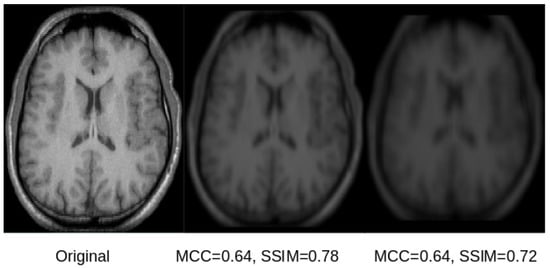

Figure 6.

A selected slice from an original MRI dataset without skull stripping (left) and its reconstruction from the latent space of the U-Net (center) and SegNet (right). As can be observed in the image, the original and the reconstructed images are overall similar. However, the reconstruction from the SegNet model is more blurry, which is reflected by lower a SSIM score, while the MCC is very similar for both reconstructions, not reflecting the differences in reconstruction quality.